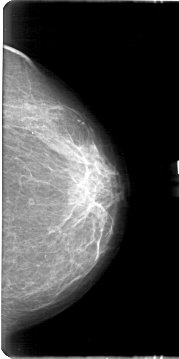

ics_version 1.0 filename D-4166-1 DATE_OF_STUDY 12 6 1997 PATIENT_AGE 44 FILM FILM_TYPE REGULAR DENSITY 2 DATE_DIGITIZED 2 6 1999 DIGITIZER HOWTEK 43.5 SEQUENCE LEFT_CC LINES 5371 PIXELS_PER_LINE 2671 BITS_PER_PIXEL 12 RESOLUTION 43.5 NON_OVERLAY LEFT_MLO LINES 5191 PIXELS_PER_LINE 2701 BITS_PER_PIXEL 12 RESOLUTION 43.5 NON_OVERLAY RIGHT_CC LINES 4786 PIXELS_PER_LINE 2416 BITS_PER_PIXEL 12 RESOLUTION 43.5 OVERLAY RIGHT_MLO LINES 4906 PIXELS_PER_LINE 2836 BITS_PER_PIXEL 12 RESOLUTION 43.5 OVERLAY |